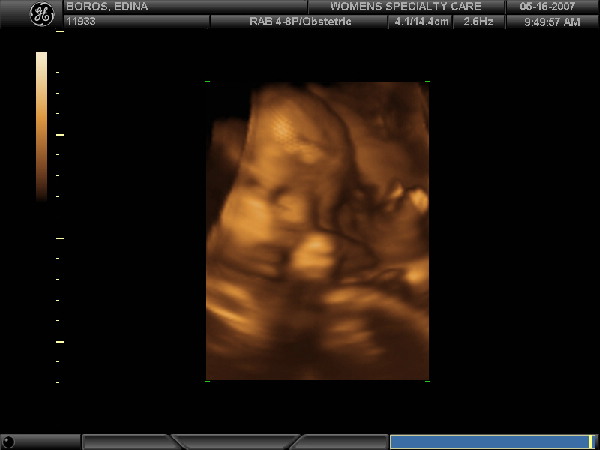

Ma voltam dokinál, babát 2200 gr-ra becsülte, szerinte nagyobb lesz, mint Péter (Ő 2650 volt), de persze nem óriási. Csoda is lenne, mert hízásban még mindig csak az 5 kg-nál tartok.